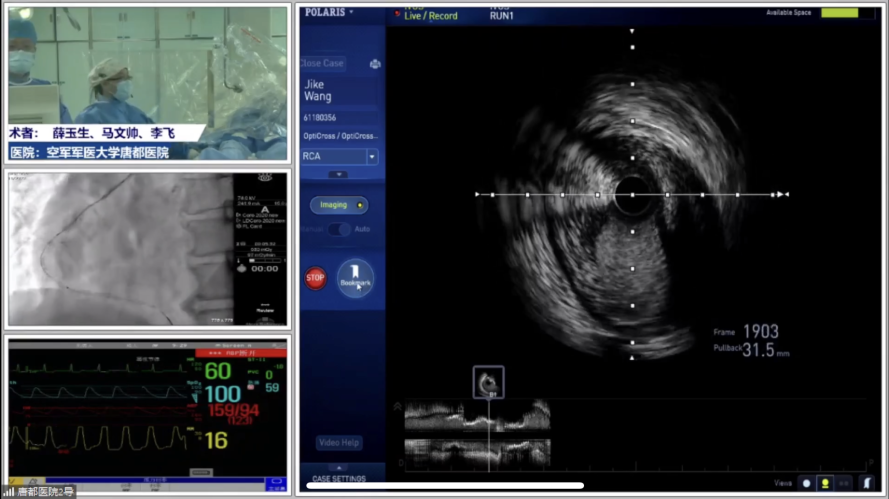

GZ支撑妙用集锦之二:曲径通幽,一路坦途

第二环节由广东省人民医院何鹏程教授、中国医科大学附属盛京医院庞文跃教授、宁夏医科大学总医院心脑血管病医院仇玉民教授共同主持,渭南市中心医院江红教授、空军军医大学唐都医院薛玉刚教授、王彬教授、楚轶教授参与讨论,围绕PCI难关——迂曲病变,西安交通大学第一附属医院雷新军教授张勇教授分别分享了Guidezilla妙用及经典病例,空军军医大学唐都医院李妍教授团队,薛玉生教授带来高难度迂曲病变PCI的精彩手术演示。

图片

Guidezilla最重要的应用指征是钙化和迂曲病变。当术者面临极度迂曲的钙化病变时应该主动积极启用Guidezilla,方能在曲径中开辟坦途。在此类病变应用中Guidezilla的规范化操作可以有效避免器械输送相关难题及并发症。球囊辅助的滑行和追踪技术(BAT)通过将直径较小的半顺应性球囊置于Guidezilla前方,低压力扩张,在球囊释放压力时引导Guidezilla跟进和前行,帮助延长导管滑过迂曲段,使导管前行更加高效和安全。因此,唯有规范化操作Guidezilla才能使其发挥价值。

俗话说,天不怕地不怕,就怕迂曲加钙化,张勇教授分享的病例就是一例极度迂曲合并钙化的高难度三支病变。该患者LAD近段扭曲,开口位置显示不清,中段次全闭塞,合并钙化及慢血流;LCX开口病变;RCA近段迂曲,中段重度狭窄伴钙化。结合其它辅助检查确定LAD为此次罪犯血管,于是选用强支撑Guiding送入Finecross微导管,升级导丝通过闭塞段,并使用小球囊扩张中段病变;随后启用平行导丝技术,但导丝无法送入LAD远端,小球囊也无法通过近段扭曲处。术者立即启用Guidezilla提供辅助,串联植入两枚支架并后扩张。2月后再次处理RCA病变时考虑到钙化迂曲影响器械通过,术者主动启用Guidezilla辅助球囊扩张及支架植入,顺利完成手术。

对于严重迂曲钙化的病变,Guidezilla可以解决器械输送的难题,并为患者安全护航,李妍教授团队,薛玉生教授手术演示的病例同样体现了这一点。该患者为一名中年男性,冠脉造影示RCA全程迂曲,中段支架以近及以远均可见到狭窄病变,3段起始处狭窄90%,其后合并瘤样扩张。术者预判病变通过困难,需要Guidezilla提供支撑。手术过程中首先使用小球囊扩张近中段狭窄病变,随后使用球囊引入Guidezilla,并在Guidezilla辅助下成功将小球囊送入最狭窄处进行有效扩张并植入支架。

随后出于稳定血流动力学的考虑,术者撤除Guidezilla,在近中段串联植入第二枚支架时发生了支架脱载。术者反应迅速,多次后扩张成功挽救,最终保证了良好的手术效果。这一病例充分体现在迂曲病变PCI中全程使用Guidezilla提供强支撑的价值。